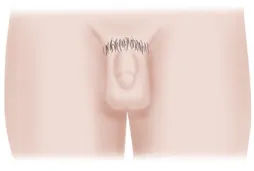

남아

남아의 경우

1단계

고환에 변화는 없으며

음모가 없음

2단계

고환이 커지고 음낭이 착색되며, 음경이 약간 커지고 음경 저부에 긴 솜털이 나옴

3단계

고환과 음경이 커지고 음경이 길어지며, 음모의 수가 많고 곱슬곱슬해짐

4단계

고환과 음경이 커지고, 길고 굵어짐 음모는 성인형이나 털 분포가 좁음

5단계

고환과 음경이 어른의 크기이며, 음모는 대퇴내측까지 넓게 남

여아의 경우 유방과 유두가 조금 부풀거나 음순주위에 솜털이 나는지

남아의 경우 성기가 커지고 음낭에 착색이 생기고 솜털이 나는지 꼭 체크해보세요.